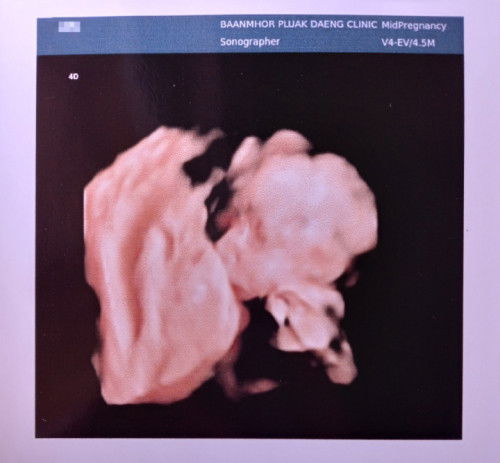

พอดีเรามีเลือดออกเลยไป รพ อายุครรภ์6week 6day โดยประมาณ ได้ซาวผ่านช่องคลอดดูถุงอยู่ในมดลูกถุงสวยดูปกติดีแต่ไม่เจอตัวเด็กหมอบอกน้องอาจะยังเล็กอีกอาทิตย์ให้มาซาวใหม่แอบกังวลค่ะแท้งมา2ท้องติดแล้วกลัวท้องลม🥺 #แม่ๆบ้านไหนมีภาพซาวด์ตอน6วีคมาแบ่งปันกันได้นะคะ อัพเดตค่ะ26/01/2023 เจอน้องแล้วค่ะอายุครรภ์7วีค1วัน อายุครรภ์ไม่ตรงกับประจำเดือนห่างกัน1สัปดาห์ค่ะ ได้ยินเสียงหัวใจแล้วค่ะดีใจมากๆ🥰 #แนบรูปให้อยู่ในภาพที่2นะคะ